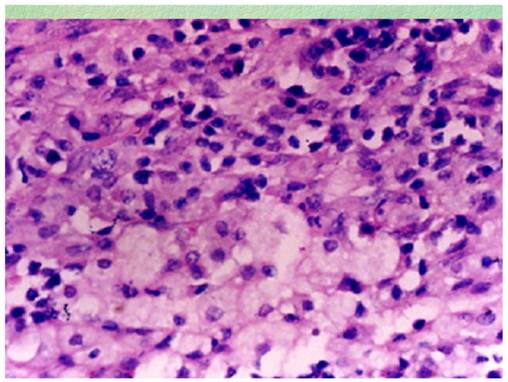

Figure 1

Effaced ovarian structure with dense chronic inflammatory cellular infiltrate (case 1).

Microscopic examination: All specimens were fixed in 10% formalin, dehydrated in descending grades of alcohol, sections were paraffin embedded and processed for histologic and immunohistochemical stains. The pathological changes were composed of mixed inflammatory cells and focal foamy histiocytes. The inflammatory cells were mainly lymphocytes admixed with plasma cells, small number of neutrophils and eosinophils (Figure 1). The foamy histiocytes were focally scattered, with abundant cytoplasm, small lipid vacuoles and hypochromatic nuclei (Figure 2). Multinucleated giant cells were not observed. In the stroma, fibroplasia with fibrosis, vascular proliferation with sclerosis in arterioles, hyperplasia and swelling in blood capillary endothelial lining were observed. The fibrous pseudocapsule was infiltrated with chronic inflammatory cells. Periodic acid-schiff (PAS) and acid fast stains were negative. The subsequent immunohistochemical stains demonstrated positive CD20, CD5, CD79a, κ and λ. The pathological diagnosis rendered as xanthogranulomatous oophoritis.